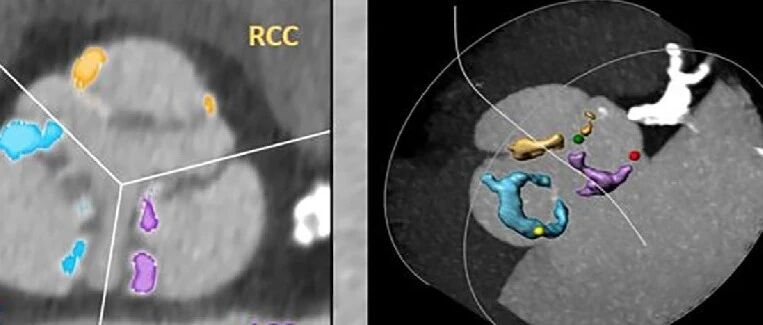

TAVI并发症-永久起搏器植入风险预测三要素